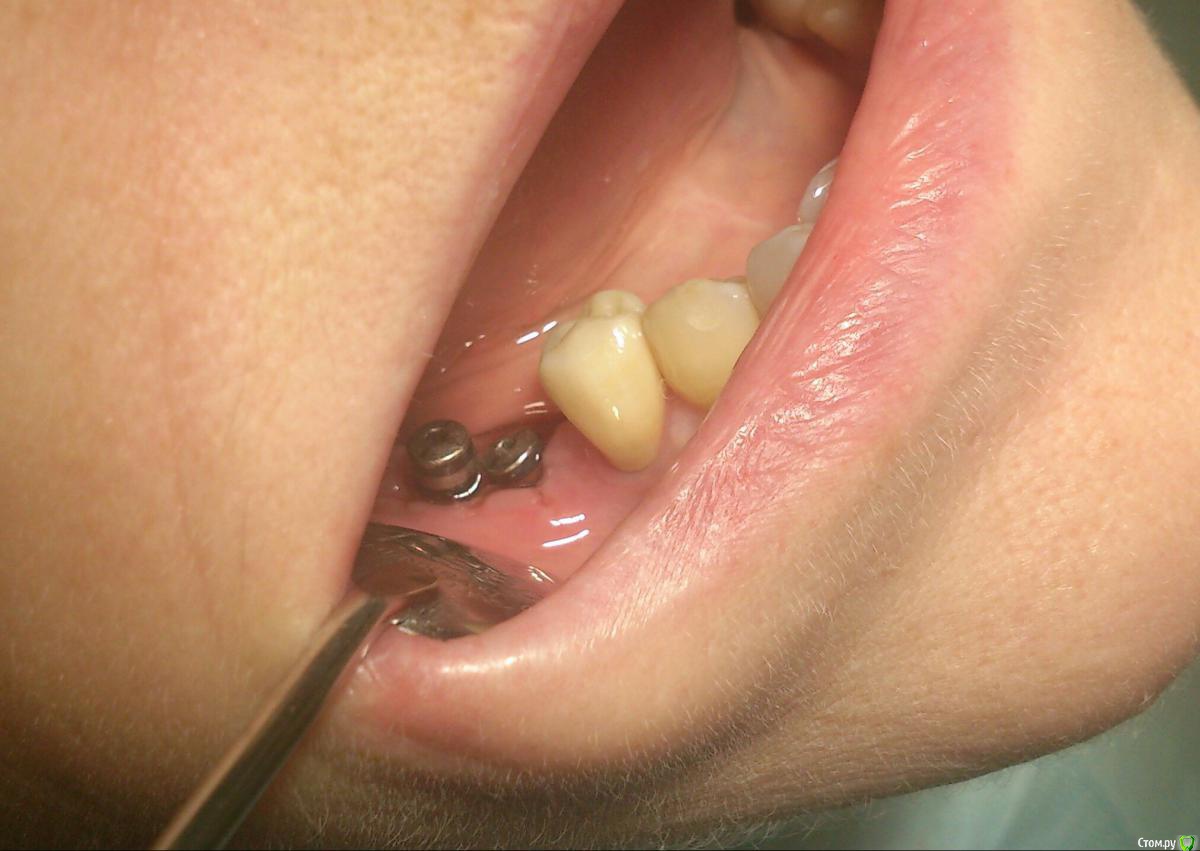

andrey_1965 Опубликовано 21 декабря, 2015 Поделиться Опубликовано 21 декабря, 2015 Ну как результат ?1.-диэпителизация подворот лоскута очень удобно,но опасно для резбы через неделю.язычно-механическая травма через 10 дней через 3недели. На временных доформирую рельеф.2. вроде ничего нештатного через 2недели A-PRF через 5недель убрал все,закрыл мембраной A-PRF две поперек,одна в доль через неделю через 13дней через 21день. Следующий осмотр будет на сроке 5 недель(думаю все сравняется) 3. через неделю 2недели 3недели,на дистальных отмываю помойку4 недели Ссылка на комментарий